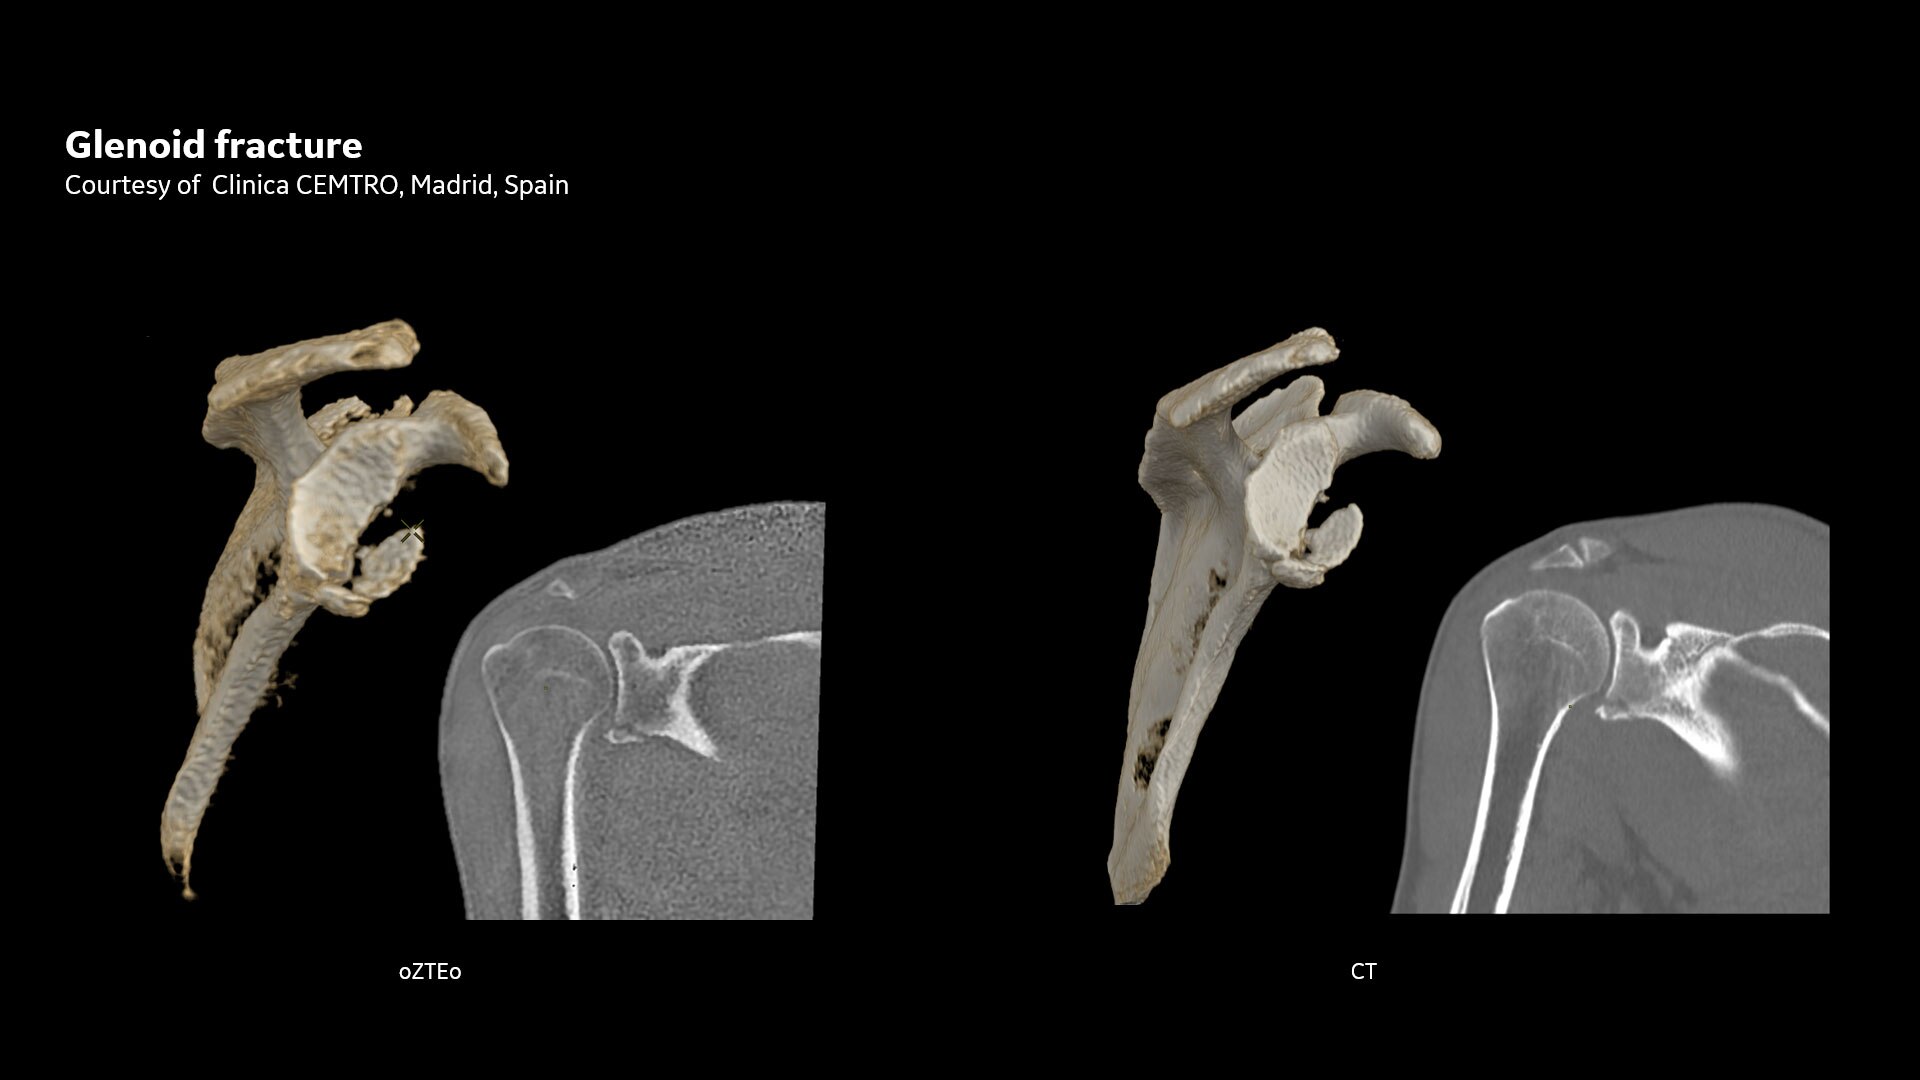

Powerful bone imaging for all anatomies

Available for all anatomies without ionizing radiation, oZTEo delivers images of bone morphology, calcification, ossification and fractures. oZTEo complements conventional MR soft tissue exams with perfect co-registration and provides 3D isotropic imaging using a radial ZTE acquisition, with inherent motion insensitivity. Use oZTEo with Volume Illumination for realistic 3D rendering.